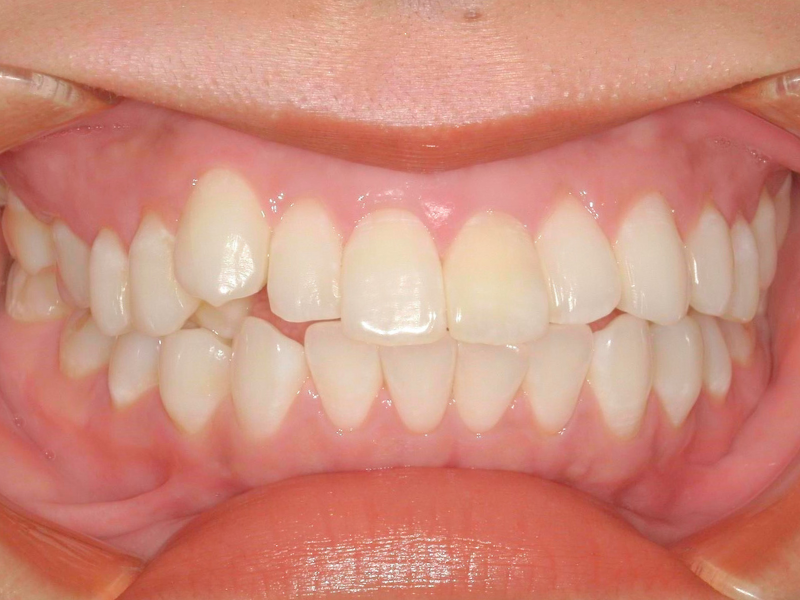

20代、女性、ワイヤー

| 施術内容 | 主訴:口ゴボが気になる。 詳細:ワイヤー矯正での歯並び改善 口元がかなり変化し、とても満足された症例です。 |

| 治療期間 | 16ヶ月(3/24現在 治療終了) |

| 費用 | ワイヤー矯正 60万円(税込660,000円) |